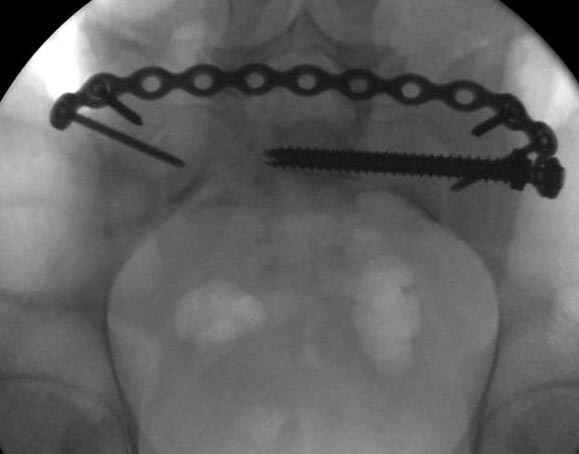

Здесь слайды случая больного с политравмой, включающей сегментарный перелом бедра и повреждение таза с нарушением тазового кольца, разрыв симфиза и перелома крестца зон 2 и 3.

На множественных слайдах важные моменты операции. Хотел бы подчеркнуть, как важно иметь возможности всех необходимых ренгенограмм, включая компютерную томографию и стандартных внутритазовых рентгенограмм (инлет и оутлет).